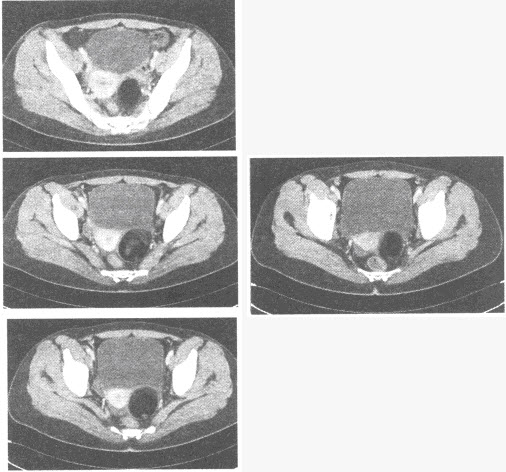

患者,男,56岁。因背部疼痛2个月入院;查体:胸椎T~T棘突和椎旁有压痛,胸椎活动受限。体温38.4℃,X线平片和CT见下图。

下列哪几项支持诊断()

A:椎间隙变窄

B:椎旁脓肿

C:椎间盘受累

D:呈跳跃性累及多个不相邻病灶

E:骨质破坏

F:阳性椎弓根征

女,35岁,下腹部胀痛,CT扫描如图所示,盆腔内囊实性肿块影,其内CT值不均,CT值-120~360HU不等,最可能的诊断是()

A:子宫肌瘤

B:卵巢癌

C:卵巢畸胎瘤

D:卵巢囊肿

E:以上都不是